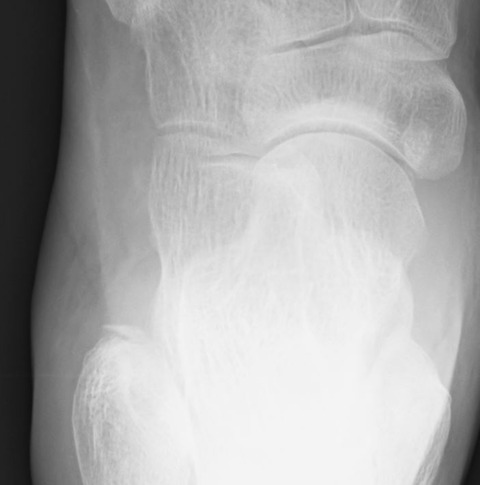

圧痛の最強点は足関節外側靱帯部およびリスフラン関節部のようです。さしあたって単純X線像を確認しましたが、明らかな異常所見を認めませんでした。

リスフラン関節部にも明らかな骨折はなさそうです。靱帯損傷なんだろうな~と思っていると、足部正面像で腓骨遠位端に裂離骨折がうつっているではありませんか!

なるほど、足関節外果部の圧痛はコレだな。。。実はこのようなことは今回が初めてではありません。何度か足部正面像で腓骨遠位端の裂離骨折をみつけたことがあります。

おそらく踵腓靭帯性裂離骨折であれば、足関節正面像でも分かると思いますが、前距腓靭帯性裂離骨折は足関節正面像では分かりにくいのでしょう。

ルーチンで足部正面像を撮像する必要は無いと思いますが、足部捻挫と紛らわしくて撮像する際には、腓骨遠位端も確認した方が良いと思います。